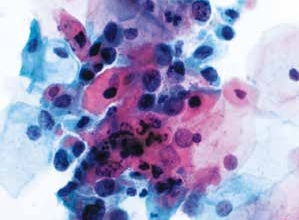

2. 非角化型鳞状细胞癌(non-keratinized squamous cell carcinoma)(图4-65~4-70)

图4-65 非角化型鳞癌(高倍、液基、巴氏染色)

明显的肿瘤素质,癌细胞成团,形态多样,核大,深染,染色质粗颗粒状,胞质蓝染。